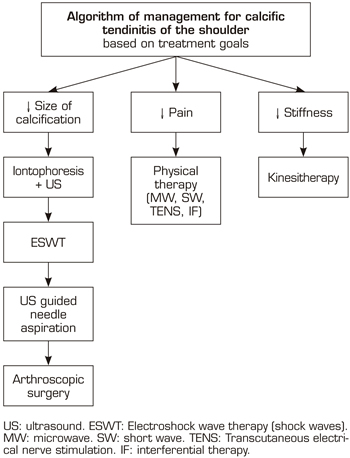

In our series, after the applied treatment, only 2.1% out of 10.8% presenting functional limitation (n = 15) remained with shoulder stiffness (n = 3), thus requiring manual therapy later. Although it was not the objective of this study, we should mention that after 20 sessions of manual therapy (on average), all patients regained their mobility (n = 3). With this in mind, we have recently proposed in a review article, a treatment algorithm for shoulder CT, in which we suggest that patients with functional limitation should undergo manual therapy (kinesitherapy) (32). In addition, patients with pain can improve these symptoms with different rehabilitation techniques (electrotherapy, thermotherapy, etc.). Whereas, for the definitive resolution of calcification, iontophoresis with acetic acid constitutes a first-line non-invasive rehabilitation modality (32). Second-line treatments include shock waves. In case of failure of the previous therapies, the most invasive measures include ultrasound-guided aspiration lavage and arthroscopic surgery (32). Figure 6.

Fig. 6. Algorithm of management for calcific tendinitis of the shoulder based on treatment goals (authorized by Fernandez-Cuadros et al.) (32).